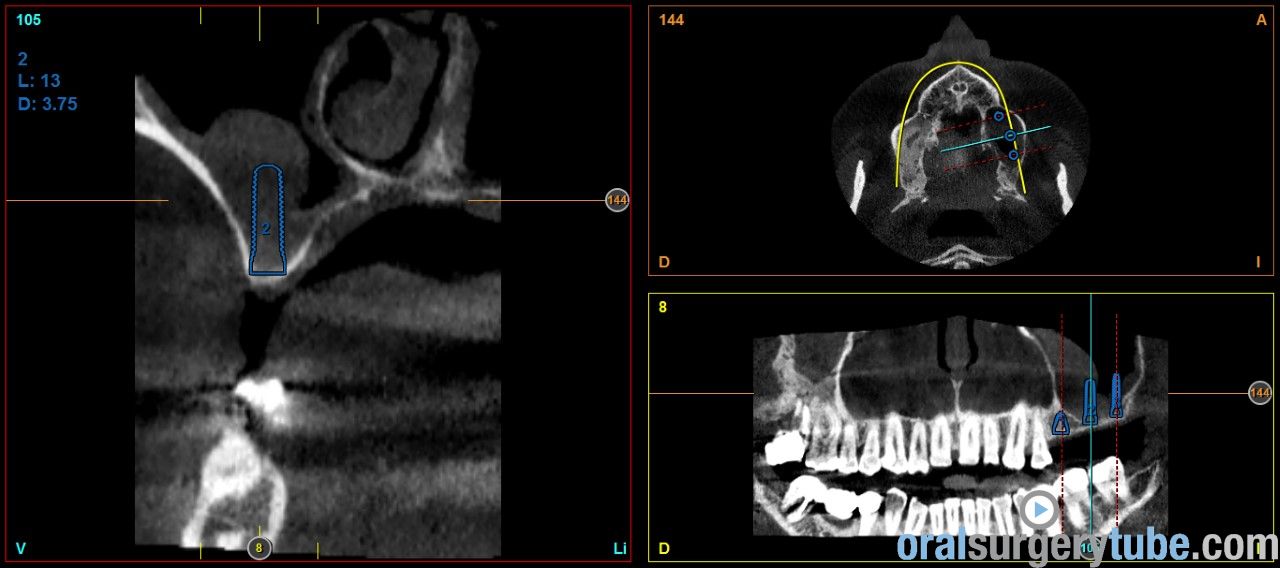

Engrosamiento mucoso

Estimados compañeros, me gustaria saber como abordaríais el seno izquierdo el cual como veis presenta engrosamiento mucoso. Haríais tratamiento previo? Gracias de antemano

Os envío imagenes. Se aprecia engrosamiento de la membrana del seno maxilar izdo.